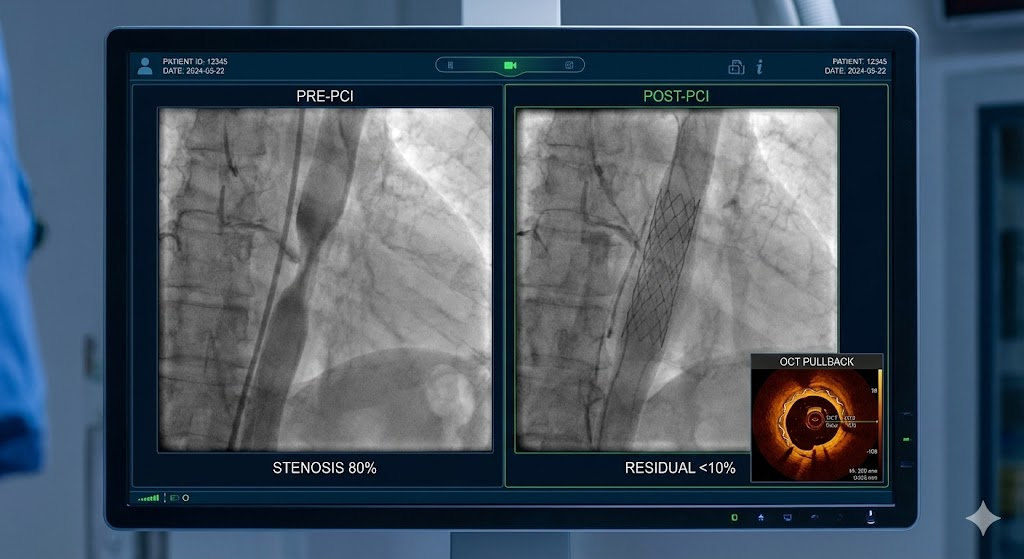

В прошлом стандартным подходом было «выстлать металлом» весь поражённый сегмент артерии — до 7 см, превращая сосуд в почти жёсткую трубку.​

Сейчас хирурги от этого уходят.

Новые принципы:

• ставить минимально необходимую длину стента, чтобы меньше нарушать естественные сокращения стенки сосуда;

• использовать оптическую когерентную томографию (ОКТ) и внутрисосудистый УЗИ, чтобы видеть, где реально начинается и заканчивается поражение;

• работать датчиками диаметром меньше миллиметра, которые позволяют ювелирно подобрать размер и расположение стента.​

Это улучшает локальный результат и снижает риск ненужного «железа» в сосуде.

Но даже идеальный стент не отменяет саму природу атеросклероза и необходимость таблеток и изменений в образе жизни.